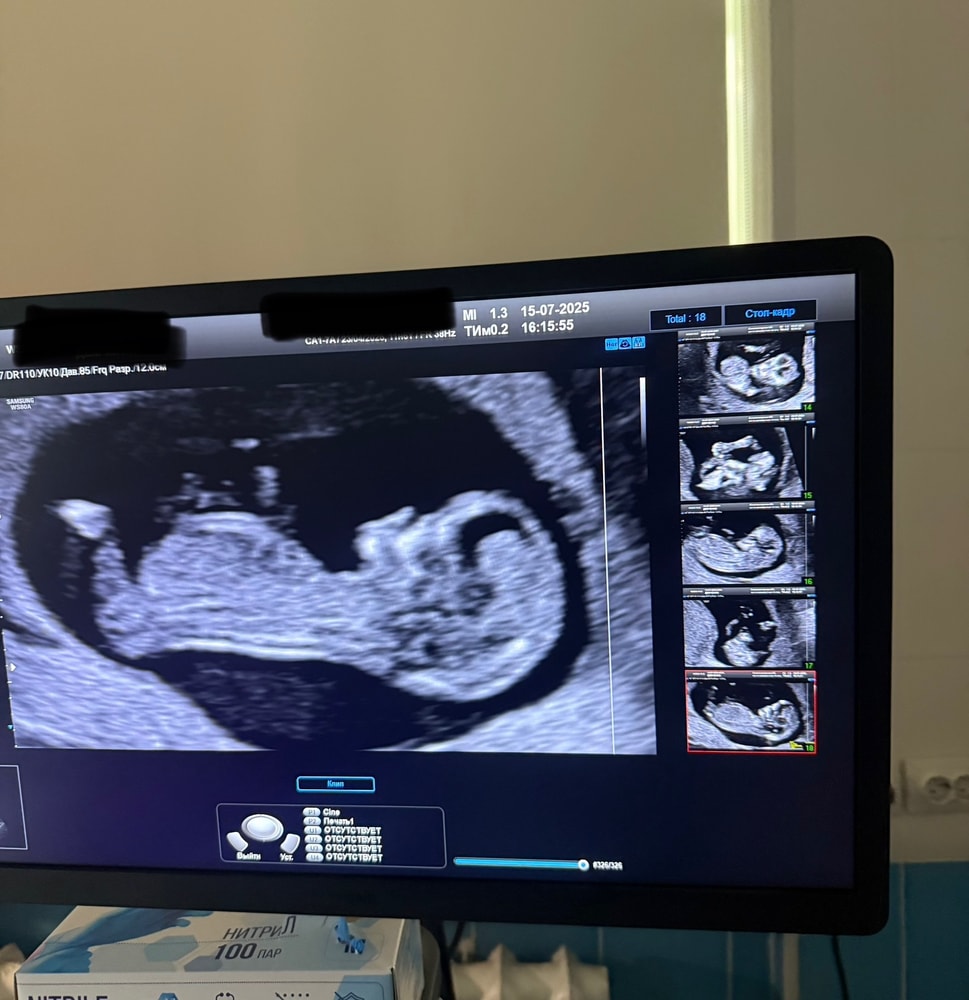

Уже после этого диалога мне стало не по себе и сейчас жалею,что не спросила у нее в чем дело.В тот момент была в своих мыслях,ждала больше всего услышать сердечко.Ведь срок маленький,а за две с половиной недели может многое поменяться.Далее она начала больно вдавливать мне этот датчик в живот и очень внимательно изучать изображение на экране.Все в гробовой тишине...🫠Я уже знатно поднапряглась и только спустя минут 5 она начала диктовать показатели и включила сердцебиение.После всей диагностики мне повернули экран и я уже увидела человечка,который активно двигал ручками и ножками,тянул пальцы в рот.Я аж расчувствовалась,впервые заплакала на узи🥺Мне дали сфотографировать экран(2 фото),тк снимок получился размытым,малыш активно двигался в процессе.Врач сказала,что все в норме и соответствует сроку,но пока рассмотреть внутренние органы трудно.Но я так понимаю,что в заключении(1 фото) она написала,что все на месте и все в норме?Имею ввиду буквы N

Еще сказала,что есть гипертонус матки.Уже не знаю,что с ним делать.В целом,я рада,что по узи с малышом все хорошо.Осталось дождаться результатов по крови.